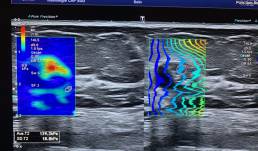

Here MammoScreen™ increases confidence in reading. A 70-year-old woman had a screening mammogram. A chest CT scan was performed 2 months before. When I biopsied the cyst with tissue content it collapsed.

To locate it secondarily in preparation for surgery I placed a biopsy clip. SBR II Infiltrating adenocarcinoma, ER/PR- HER2 status and proliferative activity pending.